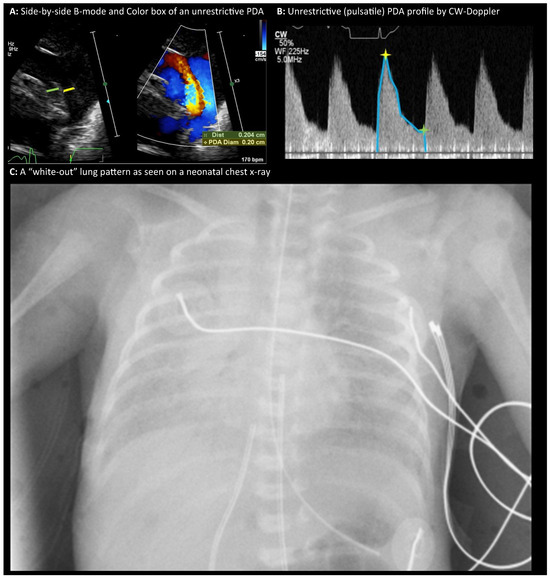

The management of patent ductus arteriosus (PDA) in premature infants remains a significant debate in neonatology. Interventions aimed at accelerating ductal closure, often using nonsteroidal anti-inflammatory drugs (NSAIDs) or acetaminophen, are common practice. However, recent evidence increasingly challenges this approach. Pharmacological agents for [...] Read more.

The management of patent ductus arteriosus (PDA) in premature infants remains a significant debate in neonatology. Interventions aimed at accelerating ductal closure, often using nonsteroidal anti-inflammatory drugs (NSAIDs) or acetaminophen, are common practice. However, recent evidence increasingly challenges this approach. Pharmacological agents for PDA closure demonstrate limited efficacy and carry significant risks of systemic toxicity, affecting renal, gastrointestinal, vascular, and pulmonary systems. Multiple recent randomized controlled trials (RCTs) and meta-analyses have largely failed to demonstrate that early active treatment improves crucial clinical outcomes such as mortality, bronchopulmonary dysplasia (BPD), intraventricular hemorrhage (IVH), or necrotizing enterocolitis (NEC). Some studies even suggest potential harm, particularly an increased risk of BPD and mortality in vulnerable extremely preterm infants. Procedural closure methods (surgical ligation, transcatheter techniques), while achieving anatomical closure, also pose significant risks and lack evidence of improved clinical outcomes. Given the high rates of spontaneous PDA closure, especially in extremely preterm infants, and the lack of proven benefit alongside potential harm from interventions, a paradigm shift towards expectant or conservative management is gaining support. This approach emphasizes supportive care, minimizing interventions, and may be complemented by the judicious use of postnatal corticosteroids in selected infants with significant lung disease, which might indirectly facilitate ductal closure by addressing underlying inflammation. Full article